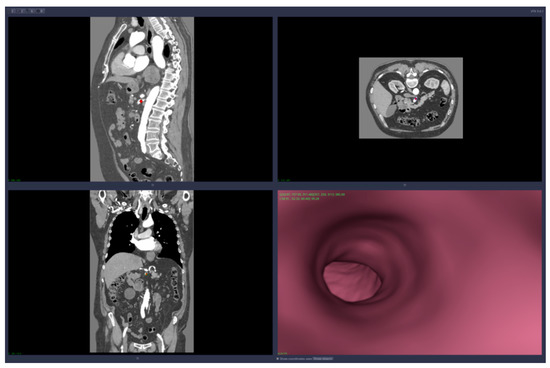

• Virtual angiography—virtual 3D navigation through the mesenteric artery and aneurysm zone (see Figure 3, Figure 4, Figure 5, Figure 6 and Figure 7)

Figure 3. Virtual angiography—“normal” zone of the mesenteric artery, before the aneurysm (direction is opposite to the blood flow).